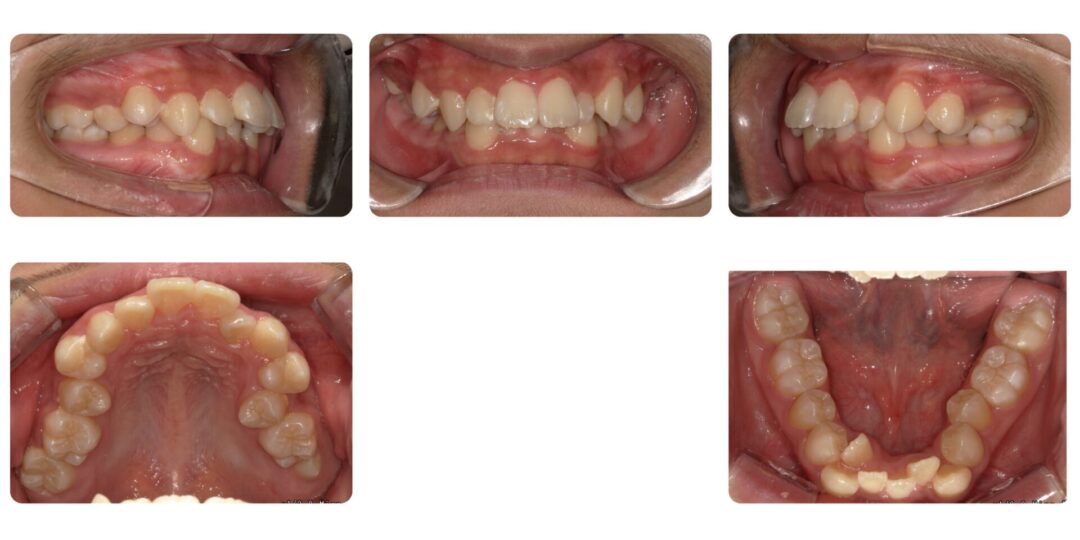

下顎前歯部重度叢生を伴う骨格性上顎前突|初診時13歳

矯正治療前

下の前歯ガタガタ気になる、上の前歯が出ている

第二期治療 上下左右4番抜歯 マルチブラケット装置による歯列矯正

2年11ヶ月